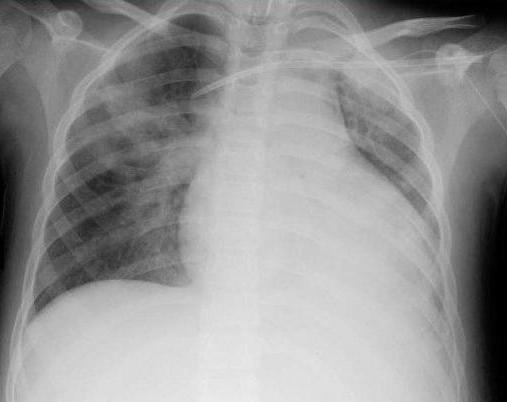

Легочное кровотечение чаще наблюдается у мужчин среднего и пожилого возраста. Оно начинается с кровохарканья или возникает внезапно, на фоне хорошего состояния. Кровь при легочном кровотечении пенистая, не свертывается.

При легочном кровотечении необходимо установить характер основного патологического процесса и определить источник кровотечения. Эта диагностика бывает иногда весьма непростой даже при использовании сложных рентгенологических и эндоскопических методов.

При выяснении анамнеза обращают внимание на болезни легких, сердца, крови. Получаемая от больного, его родственников или наблюдавших его врачей информация может иметь важное диагностическое значение. При легочном кровотечении в отличие от кровотечений из желудка или пищевода кровь выделяется с кашлем.